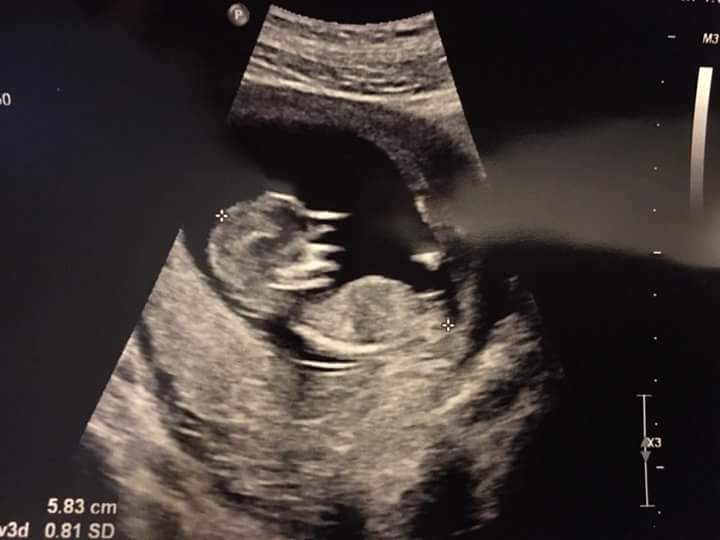

What does everyone think? Idk why but this nub is kinda tricky for me and that is exactly why i your help. This is for a friend so i appreciate all the help i can get!